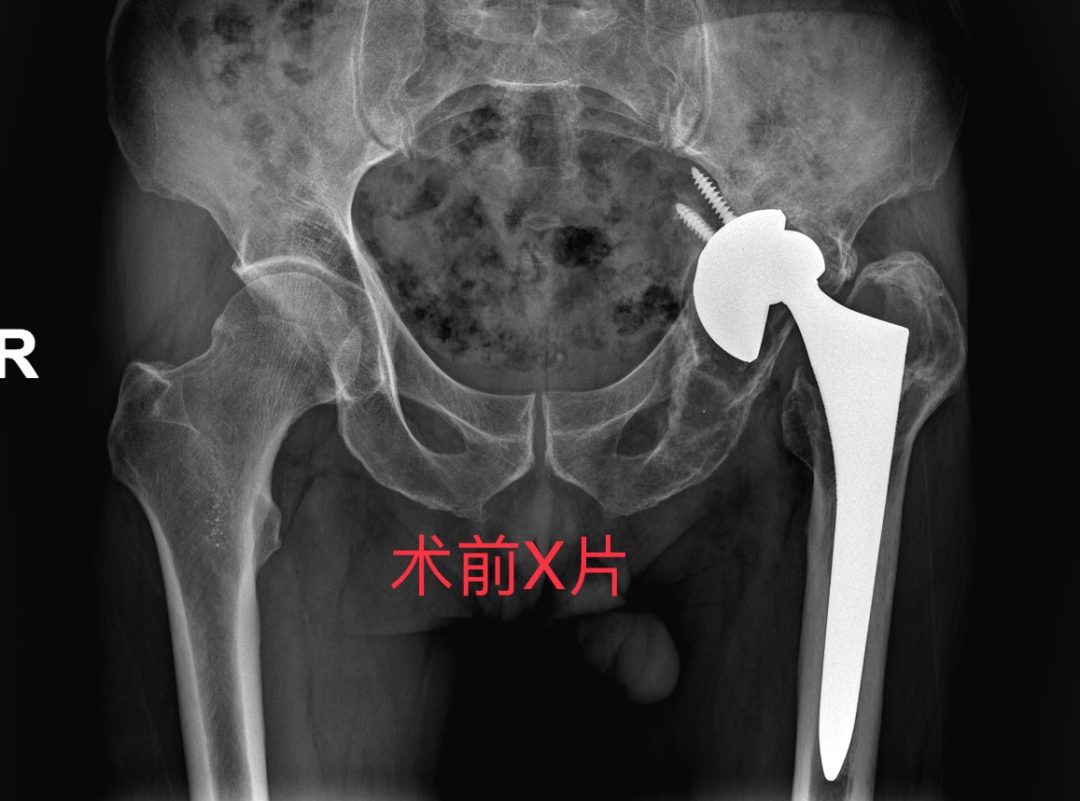

曾爷爷是一名74岁的老年男性患者,15年前因“左侧股骨头缺血性坏死”于我院骨伤科行“左侧人工全髋关节置换术”,术后康复出院。

3个月前因摔伤,导致人工髋关节假体松动、髋臼骨折、大面积骨溶解,长期卧床、生活不能自理,辗转多家医院未能得到有效治疗,不得不从外地专程赶往我院骨伤中心(关节-运动医学科)住院治疗。

入院后完善DR及CT检查后,诊断为:

1.左侧人工全髋关节置换术后假体松动

2.左侧髋臼骨缺损(PaproskyIIIB型)

3.骨质疏松

4.左髋部骨囊肿、局限积液

根据患者病情,考虑常规人工髋关节假体无法实现有效初始稳定性,而 3D 打印定制假体,能“量体裁衣” 般精准设计,突破常规手术局限,为曾爷爷量身打造独一无二的治疗方案,故选择3D打印个体化定制假体进行全髋关节翻修术。